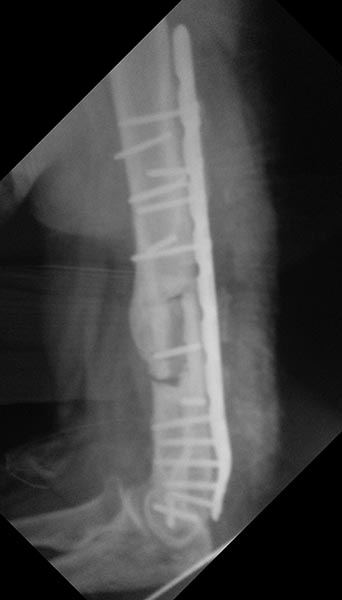

Уважаемые коллеги, хотелось бы услышать вашего мнения по поводу

непростого случая несросшегося перелома плечевой кости.

Пациент 44года в 2013г закрытый многооскольчатый перелом дистального

отдела правой плечевой кости. Остеосинтез пластинами в одной из

столичных клиник. В п/о периоде нейропатия лучевого и локтевого нервов,

за 10 месяцев лучевой полностью восстановился, локтевой почти -

небольшие парастезии в мизинце остались.

Обратился ко мне летом 2015г (по совету общего знакомого), до этого

обращался в учереждение где был выполнен остеосинтез, но в силу ряда

причин не пожелал там оперироваться (кстати предлагалось только удаление

металлофиксаторов).

цифры).В августе 2015г удаление металлофиксаторов, невролиз лучевого

нерва, реостеосинтез (той же) пластиной, но в положеном

задне-латеральном положении.

Неделю назад пациент стал говорить что появился хрукт. Рентген контроль

- перелом 2х винтов нестабильность вторичное смещение.